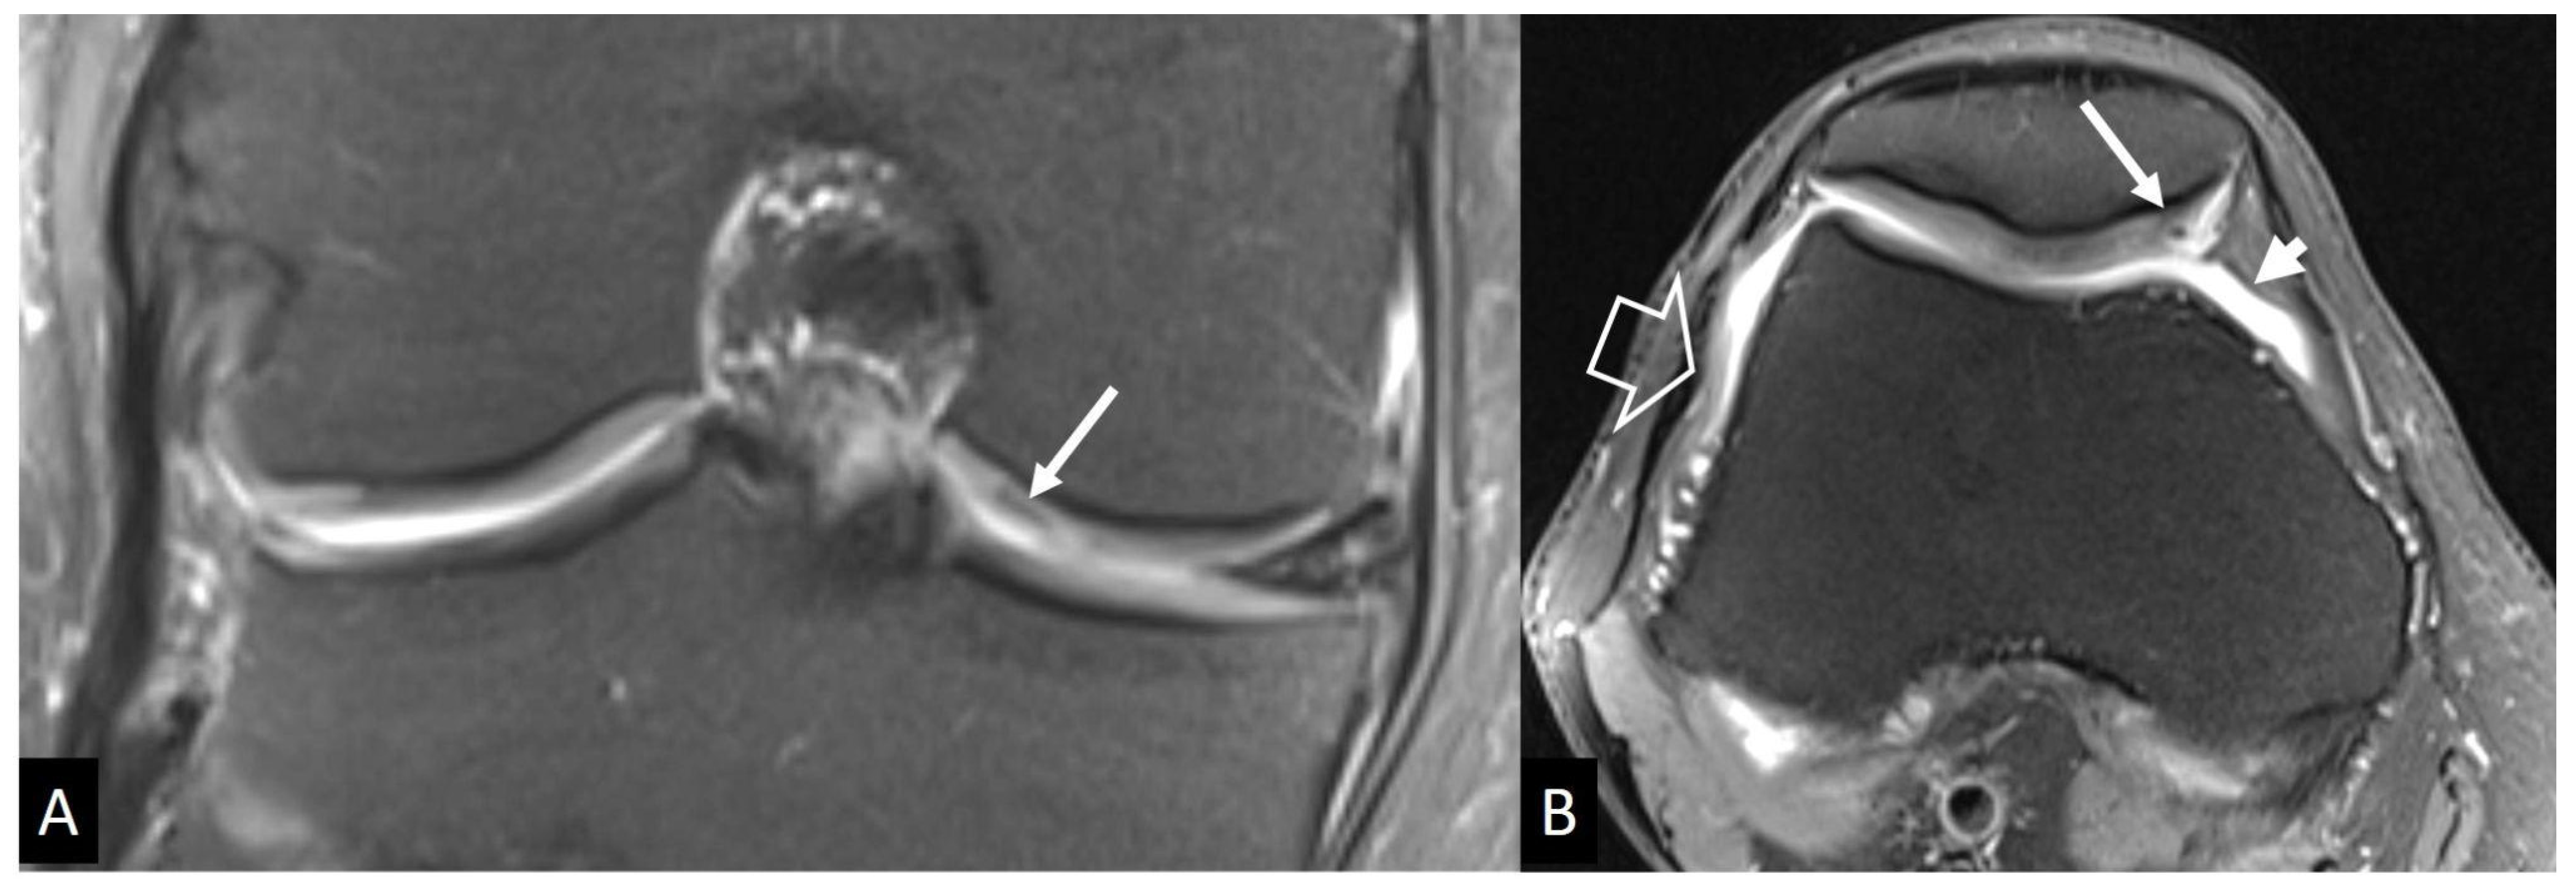

4.2.3. Crystal-Induced Arthropathies

- Buckens, C.F.; Terra, M.P.; Maas, M. Computed Tomography and MR Imaging in crystalline-induced arthropathies. Radiol. Clin. N. Am. 2017, 55, 1023–1034. [Google Scholar] [CrossRef]

- Gersing, A.S.; Schwaiger, B.J.; Heilmeier, U.; Joseph, G.B.; Facchetti, L.; Kretzschmar, M.; Lynch, J.A.; McCulloch, C.E.; Nevitt, M.C.; Steinbach, L.S.; et al. Evaluation of Chondrocalcinosis and Associated Knee Joint Degeneration Using MR Imaging: Data from the Osteoarthritis Initiative. Eur. Radiol. 2017, 27, 2497–2506. [Google Scholar] [CrossRef]